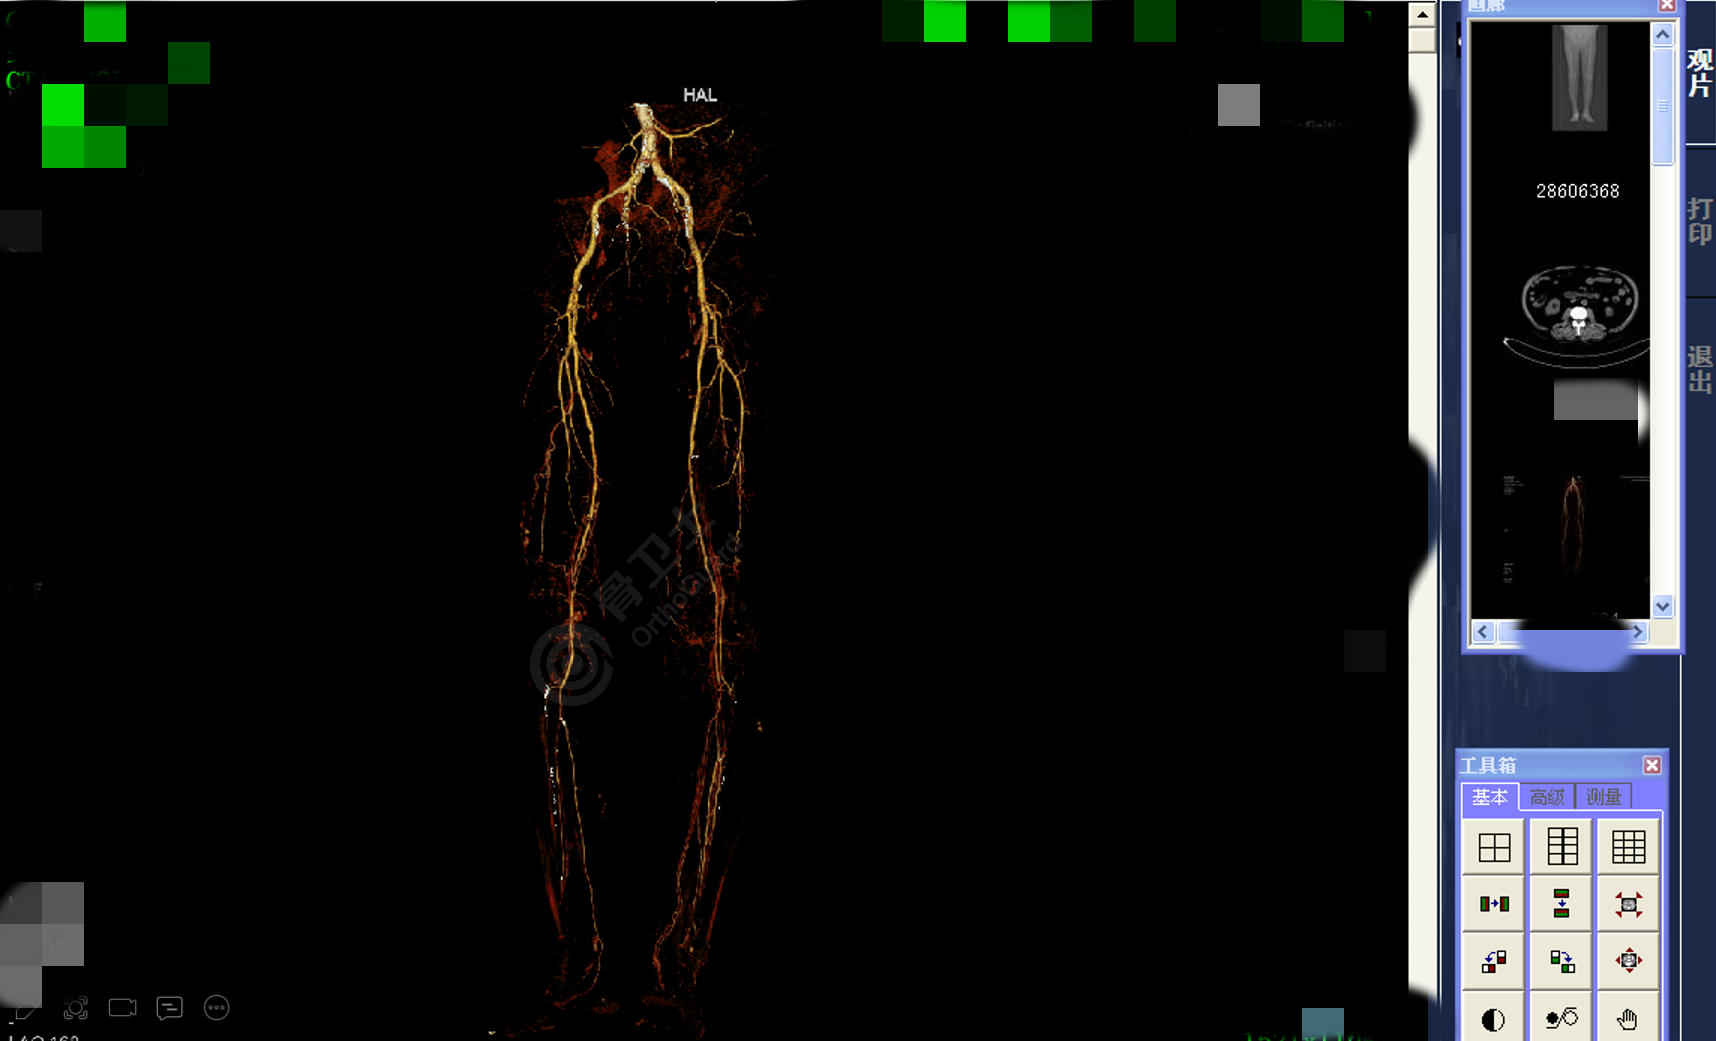

基本情况:男,59岁,因“左小腿外伤后疼痛、创口不愈半年余”入院。诊断:左小腿皮肤软组织坏死并感染,左胫骨外露,双下肢动脉重度狭窄,痛风性关节炎,2型糖尿病。治疗经过:清创术+VSD引流,使用加哌拉西林舒巴坦进行抗感染治疗,左小腿缺损创面清创,左小腿内测逆行腓肠肌皮瓣转移修复术,术后予以抗感染、抗凝血、抗血管痉挛、持续低流量吸氧改善皮瓣供养治疗,并嘱术后局部保温,红外线治疗。

▲患者影像资料

杨述华教授表示,患者本身条件很差,术前血象很高,伤口有半年不愈合,骨质外露,处理起来非常棘手。目前皮瓣的表现也还不能说完全坏死,也可能是表皮坏死,但下面可能正在愈合。皮瓣是中国在全球领先的一种治疗手段。如果患者血供比较好的话,这样处理没有问题,但患者血供比较差,皮瓣移植很有可能会感染,目前还不能完全确定皮瓣移植是否成功,还需要继续观察,可以使用一些药物加强抗菌治疗。